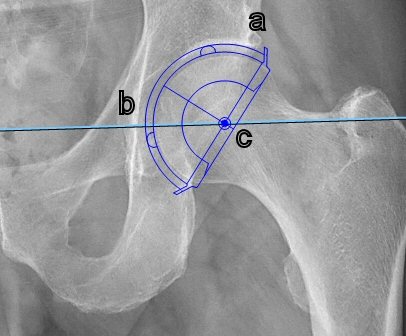

- Mät offset på frisk sida alt. gammal bild. Välj "Offfset" i "Ortho MSK", lägg linje i centrum av femur och kula med centrum i kaputs rotationscentrum. För att få korrekt värde så ska benet vara inåtroterat 15° på röntgenbilden.